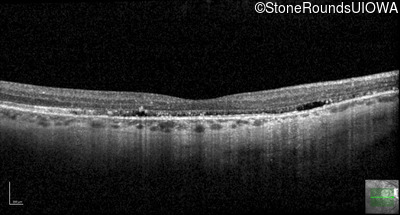

Optical Coherence Tomography - Right - 20/25 +2 sc

Exemplar / OCT Stack

OCT Stack

Optical Coherence Tomography - Left - 20/30 -2 sc